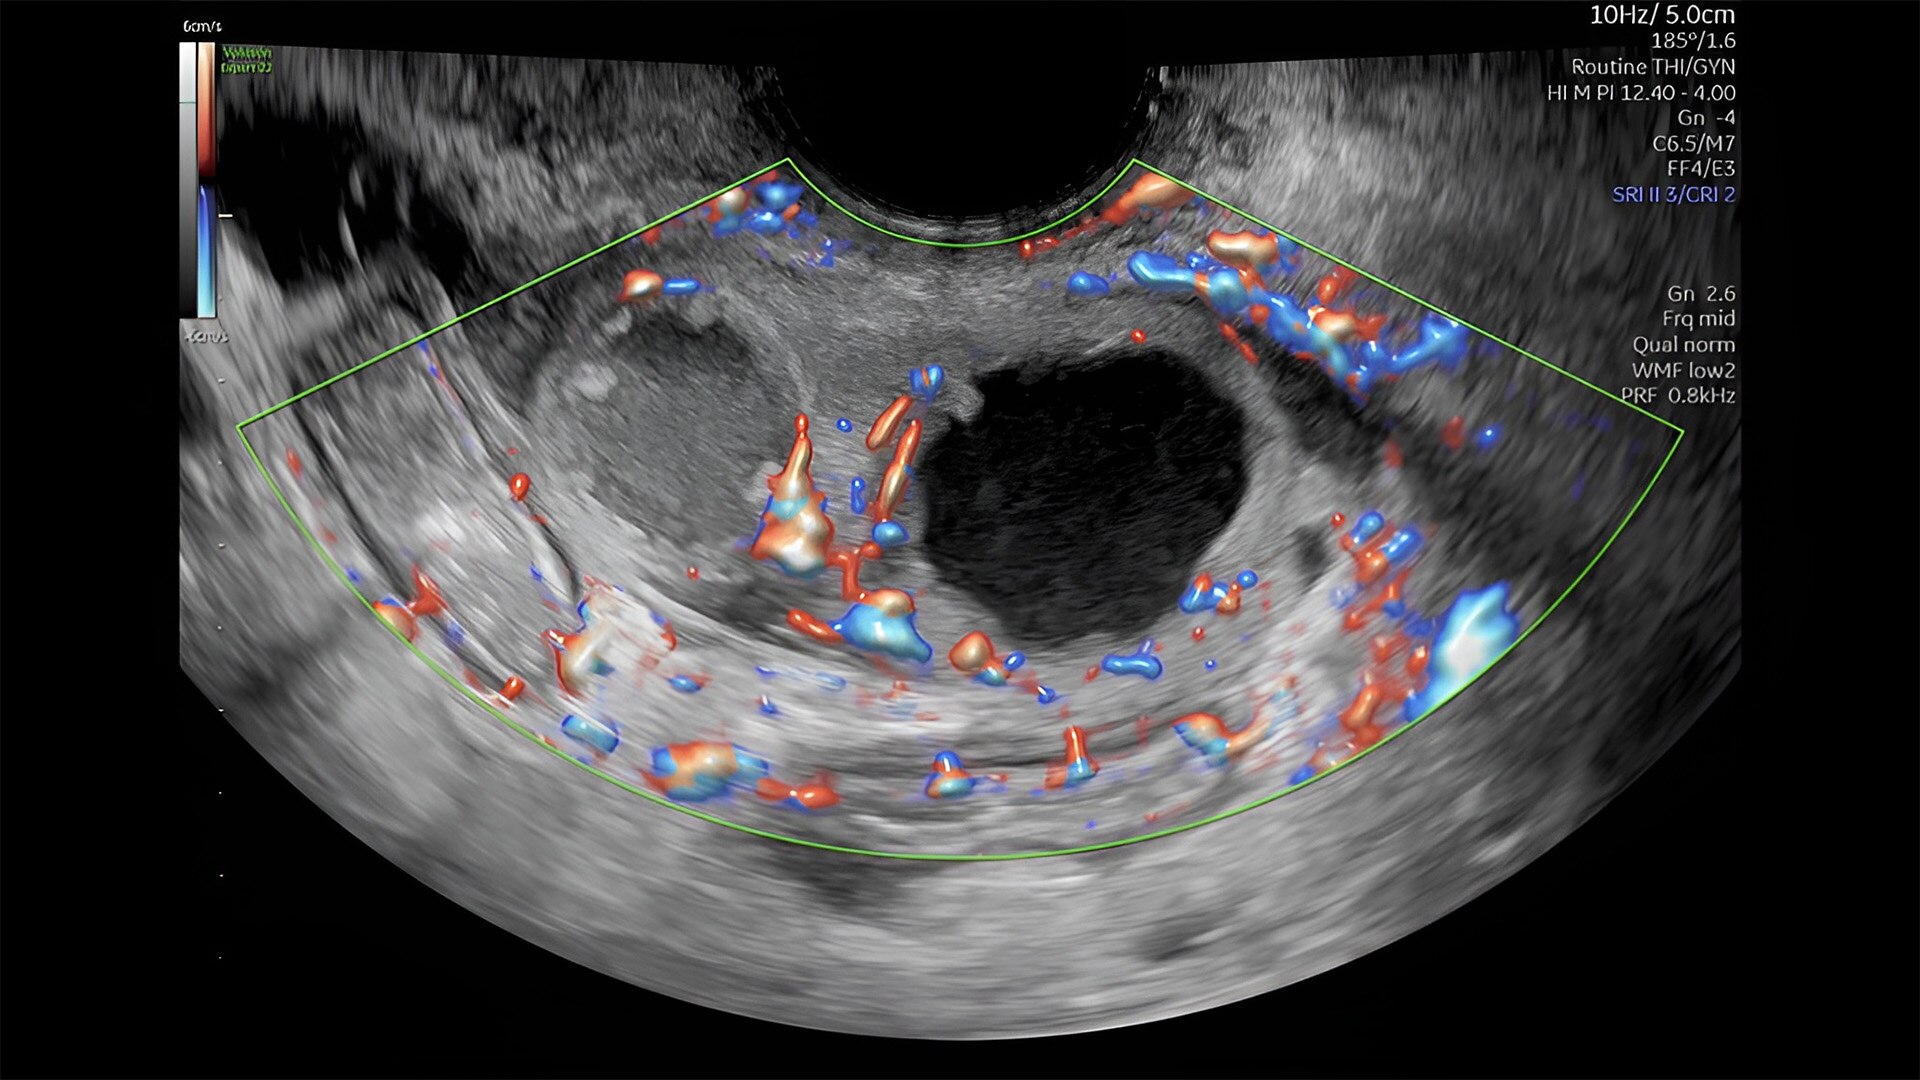

Fetal heart assessment

Detect, diagnose, and monitor with confidence using Radiant and fetalHQ

Fetal heart evaluation

Get to the heart of the matter

Identifying fetal cardiac abnormalities earlier means you can intervene sooner, plan for delivery, and potentially improve outcomes. The Voluson Expert 22 provides a full solution of progressive tools, to help distinguish the tiniest structures with stunning clarity to provide patient answers faster.